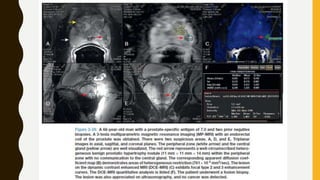

Diffusion-Weighted Imaging/Apparent Diffusion Coefficient

• DWI assesses the diffusion of water (Brownian motion) within the magnetic field. The

MR magnet is able to detect the phase shift changes in the motion of the water

protons. The more cellular a tissue is, the closer the cells are together, resulting in a

limited motion of water, which is reflected as a high signal on DWI (Manenti et al,

2006).

• As with all MR sequences, there are several details that one should observe. Most

important is the b-values associated with DWI. B-values represent a threshold for

detecting restriction. As a b-value is increased, less restricted tissues do not exhibit a

high signal on DWI.

• DWI can include multiple b-values, and it is recommended to include at least one b-

value greater than 1000 (Rosenkrantz et al, 2010). The ADC is a quantitative

assessment of the DWI. This is represented by an area of low signal on the images

(dark spot) (Fig. 2-30D). Some authors recommend including a b-2000 sequence on

DWI; it has been shown that prostate cancer exhibits a high SI compared with the rest

of the gland (Ueno et al, 2013) (Fig. 2- 30F).

• The ADC value computed from DWI has been shown to directly correlate with

score (Turkbey et al, 2011). Intuitively this makes sense because an increase in

Dynamic Contrast Enhanced Magnetic Resonance Imaging

• DCE-MRI refers to T1-weighted imaging with Gd-based contrast agents. DCE-MRI is

not a simple assessment of enhancement versus no enhancement. It assesses

permeability and perfusion of the prostate by obtaining multiple image acquisitions

over 5 to 10 minutes at a temporal resolution of less than or equal to 5 seconds

(Verma et al, 2012). The 5-second temporal resolution requires a decrease in the size

of the imaging matrix, therefore resulting in a lower resolution image. DCE- MRI is

meant to obtain clear anatomic images; it is used to assess the blood flow and

permeability throughout the gland over time. DCE-MRI provides qualitative,

semiquantitative, and quantitative information regarding enhancement within the

prostate.

• A qualitative approach consists of visually assessing early enhancement and early

washout within the prostate. The use of computer aided diagnostic systems allows

one to obtain specific information with regard to enhancement characteristics. A

semiquantitative approach assesses enhancement over time (Tofts et al, 1991). There

are three distinct curves associated with prostate imaging (Fig. 2-31). Because of the

overlap of all three curve types with benign conditions, it is useful to combine these

approaches in a MP-MRI

• A quantitative assessment for cancer was first proposed by Tofts and colleagues

(1991), observing the pharmacokinetics of the contrast within the gland. Ktrans

(transfer constant) represents the transfer rate (permeability) of contrast between the

intravascular space and the extracellular space (or blood flow) to the tissues

depending on the hemodynamics at the time of the study. Kep (rate constant) is the

rate of efflux of contrast back into the vascular space (Tofts et al, 1999). These

quantitative metrics have not been incorporated in the daily work flow of most

radiologists; however, they are currently being evaluated for possible decision analysis

software (see Fig. 2-30C, D, E, H). DCE-MRI has a reported 46% to 96% sensitivity and